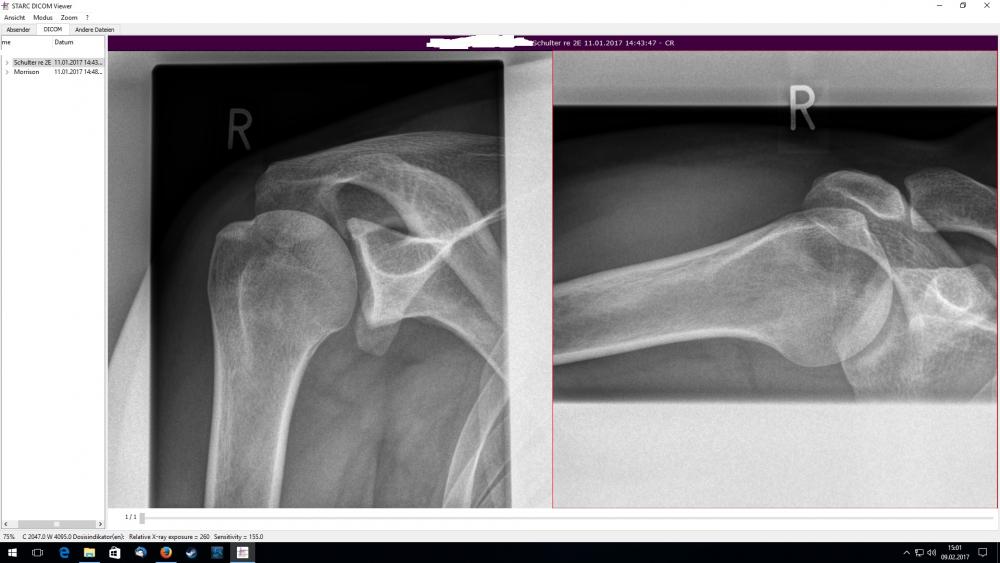

Moin, ich hoffe hier kann mir einer weiterhelfen mit meiner Schulter. Habe schon seit über 16 Jahren Probleme mit meiner Schulter. Nach dem Training/Spieltagen (Handball/Faustball) war meine Schulter für 1-2 Tage fast steif und Schmerzhaft. Behandlungen:Spritze ins Gelenk,Krankengymnastik und Tens-Gerät hab ich hinter mir. Jetzt ist der Schmerz aber seit anfang Dezember 2016 durchgehend vorhanden,sobald ich den Arm bewege oder belaste, besonders beim schlafen. Es wurde jetzt beim Orthopäden "chronisches IImpingement Syndrom" diagnostiziert und habe eine Überweisung zur OP gekriegt. Der Arzt im Krankenhaus war natürlich anderer Meinung und es gab (wieder) eine Spritze ins Gelenk und eine Überweisung zum Neurologen. Der Neurologe hat wie vom Arzt vermutet nichts gefunden und die Schmerzen sind auch wieder da. Vieleicht kann mir einer bei den beiden Röntgenbildern und MRT-Befund doch die These meines Orthopäden bekräftigen, da ich nächste Woche wieder einen Termin in diesem Krankenhaus habe, bei dem gleichen Arzt zu besprechung!!(Bericht Neurologe und wie lange die Betäubung gewirkt hat) Viele Grüße Tobias